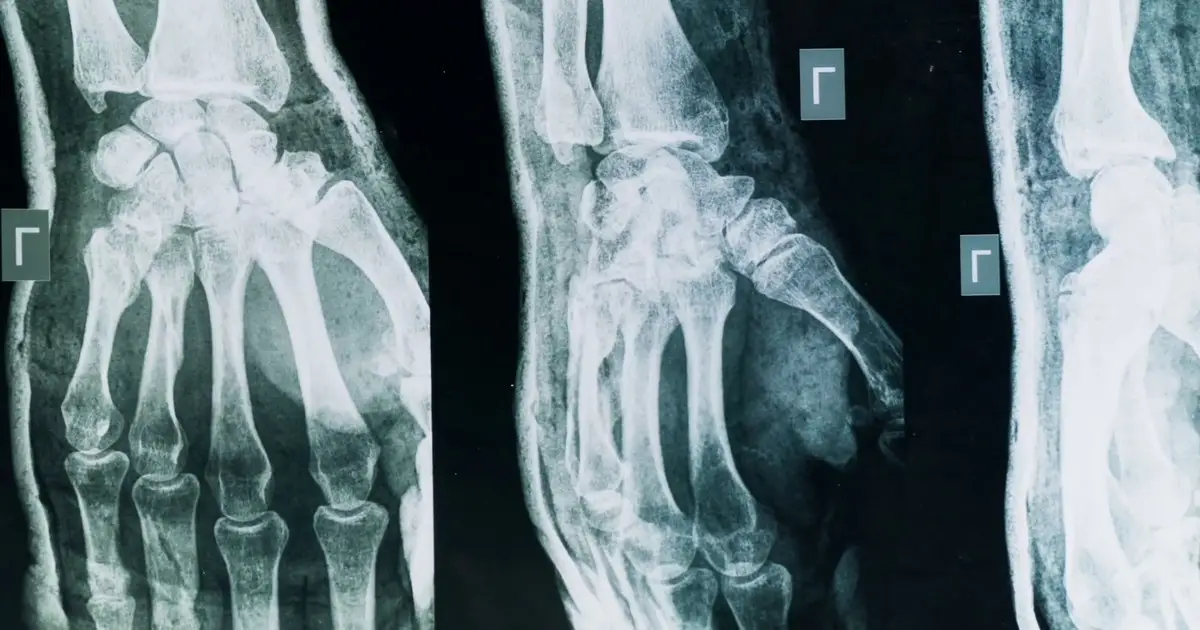

Artrite e artrosi, come riconoscerle e curarle

Artrosi, tutti i segnali per riconoscerla